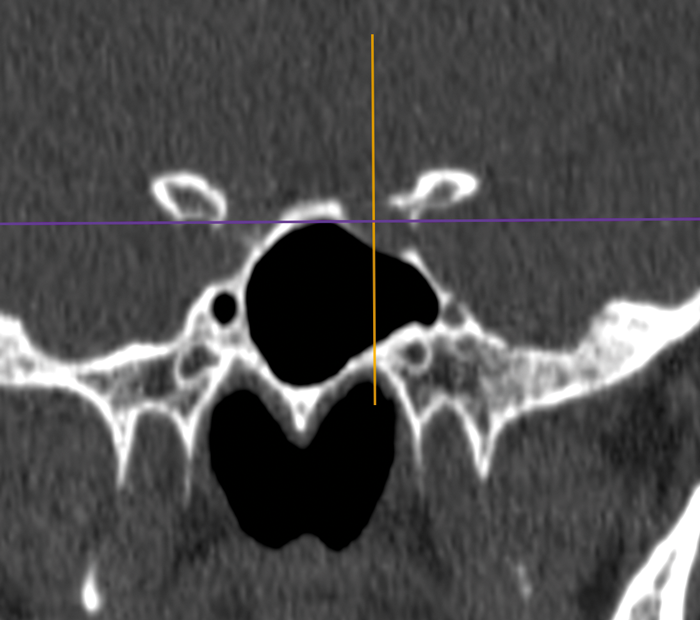

Preoperative sinonasal CT imaging is essential to FESS surgery. Ideally the CT data should be provided in thin-slices (less than 1mm thick) including the full volume of the paranasal sinuses. The images should be available during surgery in a 3 axis viewer, preferably one with the facility for multiplanar reconstruction (MPR).

Before the case, it is helpful to perform an MPR to align the axial slices with the palate and skull-base, while correcting any angulation of the coronal images to obtain symmetric views. Window-levels are optimised for bone definition, rotation corrected for each view, and the views maximised by zoom. We then study the scans from three different perspectives as follows.

Sphenoid relations - especially an optic nerve or carotid within a bony or dehiscent mesentery.

Sphenoid relations.